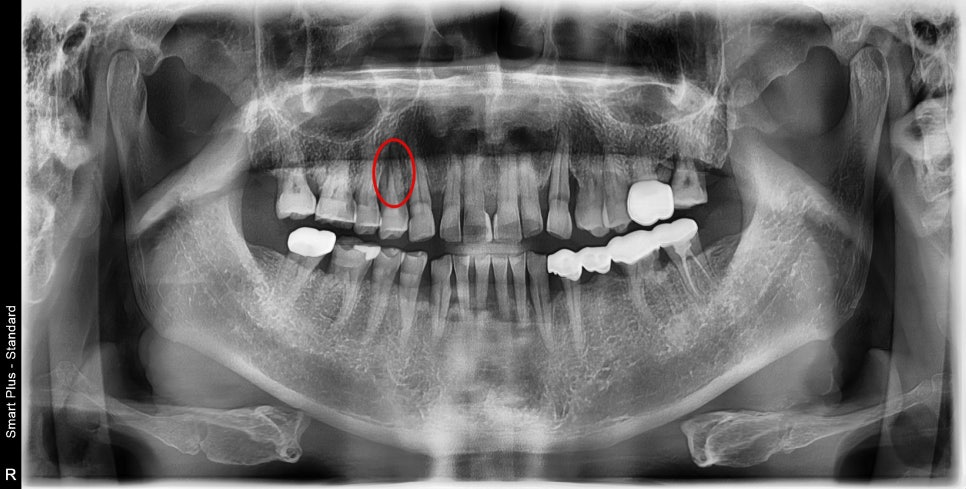

오른쪽 작은 어금니 부분이 불편하다고 내원해 주셨습니다

엑스레이에서 뭔가 뿌리 부분의 병변이 보입니다.

구강 내 사진에서는 겉으로는 전혀 문제는 없어 보이지만

건드리거나 씹을 때 통증을 호소하셨습니다.

주변 치아를 보면 평소 강한 저작력에 의한

다수의 치아 파절이 관찰되는 것을 보면

크랙에 의한 치아 동요도 및 통증이 유발된 것으로 보입니다.

3D CT를 찍어봤더니 역시나 뿌리 주변의

심한 골소실로 인한 동요도로 인한 통증으로 진단하고

환자분께는 치아의 수명이 다해서 더 이상 치료는 불가능하고

발치 후 즉시 임플란트 수술에 대해 설명드렸습니다.